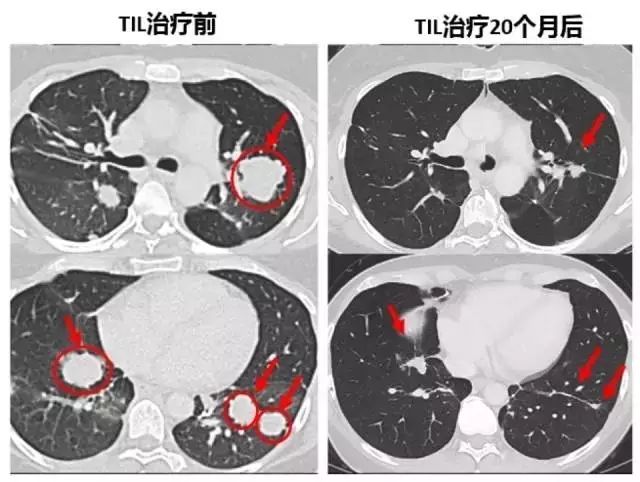

2021年8月12日,国际顶级期刊《Nature》上的一项研究引起了轰动。因为结果显示,对于PD-1治疗没有响应的临床上极难治疗的晚期肺癌患者,在使用自己的一种“特殊的”免疫细胞--TIL作为细胞疗法治疗后,竟能让部分对PD-1抑制剂没有反应的NSCLC患者获得长期的缓解,更值得振奋的是,在这项临床试验中,两名患者的肿瘤完全消失,并且持续缓解一年半以上。这意味着使用自身免疫细胞杀灭肿瘤将逐渐成为现实!

在治疗4周后,Creelan博士为她进行了CT扫描,结果显示,Pummill的肺部肿块竟然缩小了38%。治疗10个月后,再次扫描的结果显示,已经没有任何肿瘤了,Creelan博士说,她被归类为完全响应者!